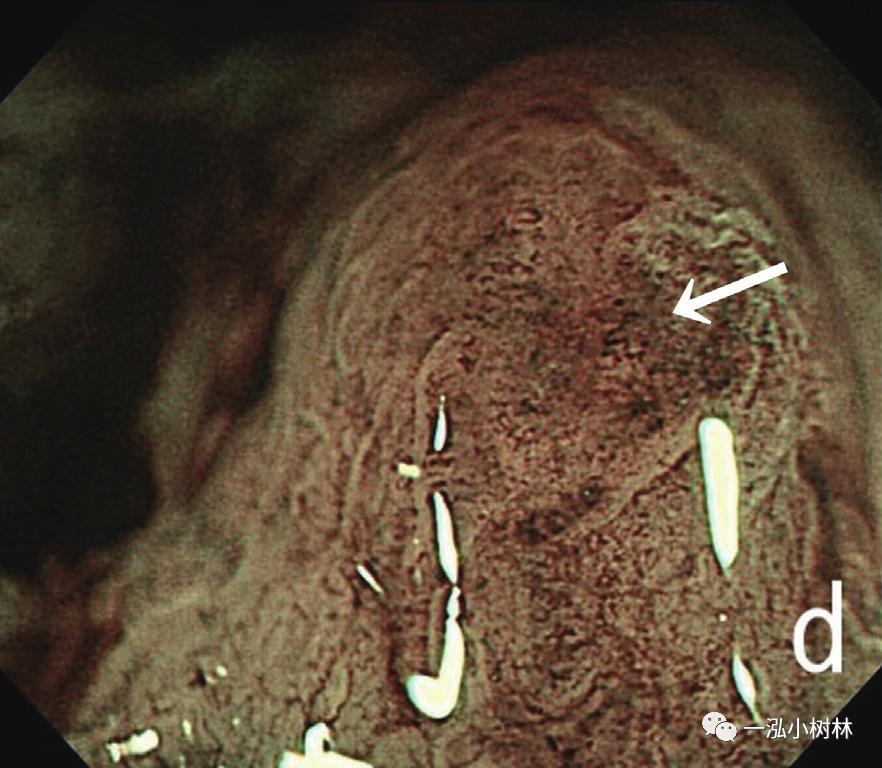

内镜检查(图1):胃黏膜整体粗糙、弥漫性隆起,易出血。在胃体下部、胃窦部黏膜的粗糙明显,散在小隆起,一部分也发现了较大的隆起性变化。ME-NBI观察即使残留着接近正常的腺管,表面微细结构的消失也很明显,在褪色区域也发现了血管的扩张和蛇行、腺管结构的紊乱。

图1d ME-NBI 贲门部 白区不清晰,微血管扩张、蛇形,分布不规则(箭头)。